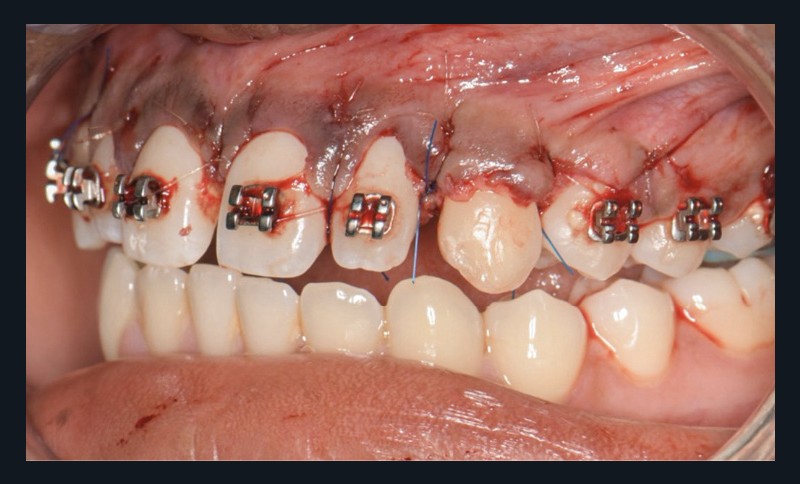

Une fois l’espace nécessaire obtenu, des cales molaires sont réalisées pour limiter les interférences occlusales avec la 23. La 63 et l’odontome sont extraits (fig. 4). Un lambeau est levé et la réplique 3D de la 23 est essayée dans l’alvéole, qui est adaptée en fonction (fig. 5). La 23 est prélevée de façon atraumatique (fig. 6) et auto-transplantée (fig. 7). Après suture du lambeau (fig. 8), une contention par arc acier 0,019×0,025’’ avec un CVI entre la dent et l’arc orthodontique est réalisée (fig. 9). Trois ou quatre semaines après l’auto-transplantation (fig. 10), le traitement endodontique est effectué (fig. 11). Un bracket orthodontique pourra être collé de façon passive, et la dent prise en charge avec un arc Niti 0,017 x 0,025’’ (fig. 12).